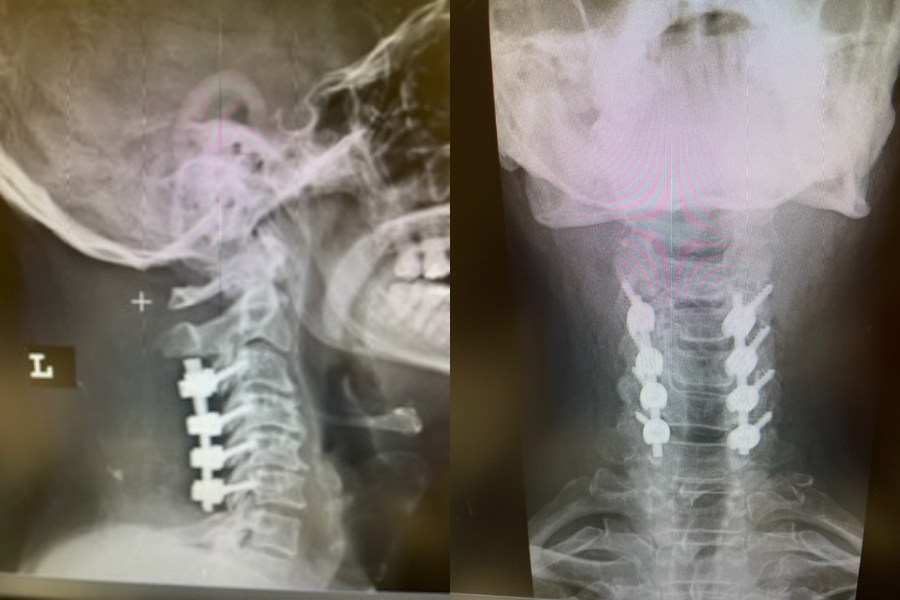

It was felt that the patient was unstable and the patient had signs of early cervical myelopathy secondary to spinal cord compression. The patient consented to undergo exploration and evacuation of the collection and to decompress and stabilize the cervical spine. Upon laminectomy we noticed a ruptured C3-4 interspinous ligament that was consistent with the preoperative imaging studies. After revealing the epidural space during the laminectomy, a large dorsal membrane or pseudomeningocele was noted above a clear fluid collection that was posterior to the dura that was compressing the spinal cord. This membrane was fenestrated and we evacuated the collection which was consistent with CSF. Also during the course of the laminectomy we noted that the source of the CSF leak to be on the left at the takeoff of the C4 nerve root for which the dural sleeve was “degloved” but the fascicles were intact. We repaired with muscle and dural sealants. We completed a C2-C7 laminectomy. The patient had an additional fusion C3-C6 with segmental instrumentation to prevent kyphotic deformity.

(3) Post operative AP and lateral cervical x-ray demonstrating good placement of hardware and alignment.

Patient did well from surgery with reduced pain in left shoulder and no further leak.(Fig. 3)